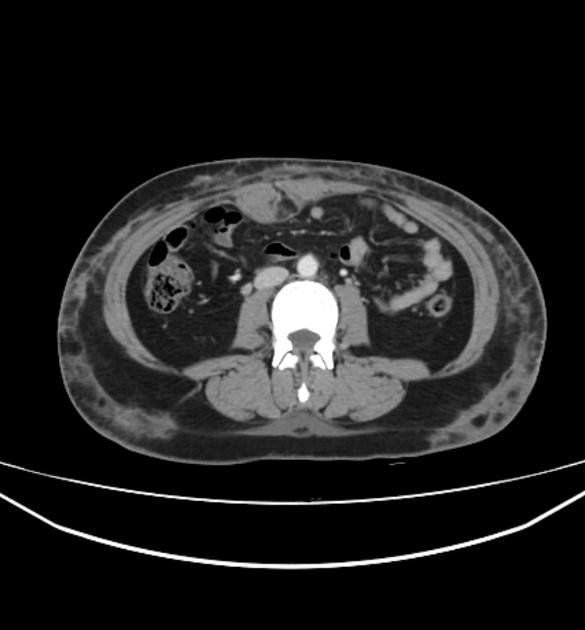

CT Scan được sử dụng để phân biệt chính xác giữa viêm mô tế bào nông và viêm mô tế bào sâu.

Trong bệnh viêm mô tế bào không biến chứng, CT cho thấy da dày lên, có các vách trong lớp mỡ dưới da và cân mạc nông bên dưới dày lên. Nếu nhiễm trùng lan đến các mô sâu hơn, áp xe mô mềm, viêm cơ nhiễm trùng, viêm cân hoại tử và viêm tủy xương đều có thể được phát hiện bằng CT.